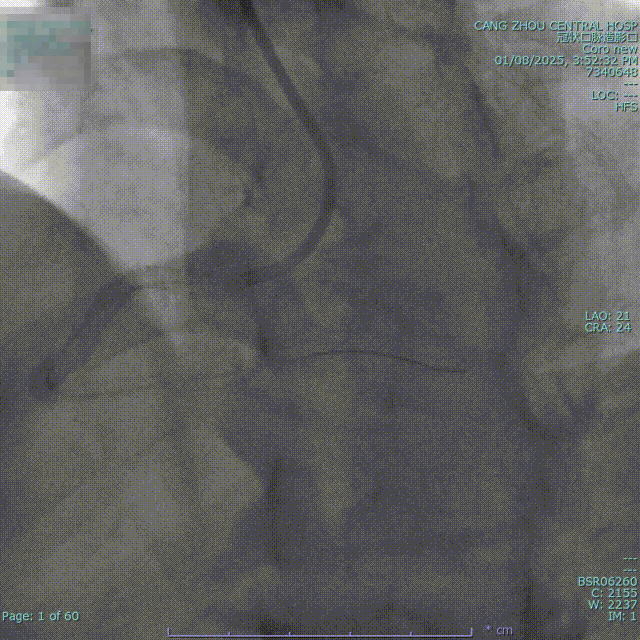

先后送入Stent 1(2.5x33mm Firebird2)、Stent 2(3.0x18mm Firebird2)、Stent 3(3.5x33mm Firebird2)、Stent 4(4.0x23mm Firekingfisher)由RCA远端至开口串联。

进入Ballon 7(3.0X12mm NC Sprinter)至Stent 1-2内由远及近以8-18atm后扩张,送入Ballon 8(4.0x12mm Grip)至Stent 3、4以12-20atm后扩。

送入IVUS导管查看支架开放良好、贴壁良好,未见夹层、血栓等 并发症。